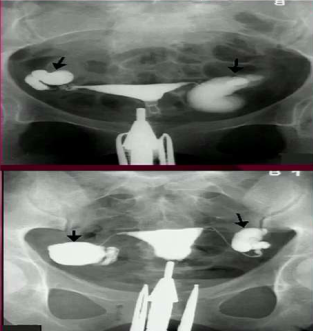

Injecting contrast into the vagina and watching it outline structures into the peritoneum

Hysterosalpingogram

How do you need to perform a hysterosalpingogram if a woman has a uterine didelphys?

Must inject beyond both cervices.